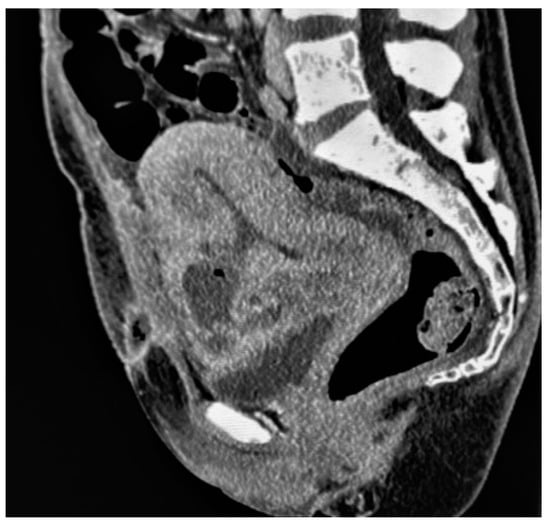

Placental/uterine bulge: deviation of the uterine serosa from the expected plane caused by abnormal bulge of placental tissue toward surrounding organs (typically toward the parametrium and bladder) can cause the uterus to take on an “hourglass” configuration due to widening of the lower uterine segment, resulting in a loss of the typical inverted pear-shape, best depicted on sagittal and/or coronal images. This finding showed a sensitivity and specificity for the diagnosis of PAS of 76.6% and 62.5% [72] (Figure 4). The specificity of this criterion increases where the bulging in the uterine contour is associated with a focal interruption of the myometrium [73].

The others four signs that did not achieve consensus (with less than 80% agreement) were classified as “uncertain”: placental protrusion into the cervix, placental ischemic infarction, placental heterogeneity, and abnormal intraplacental vascularity [73].